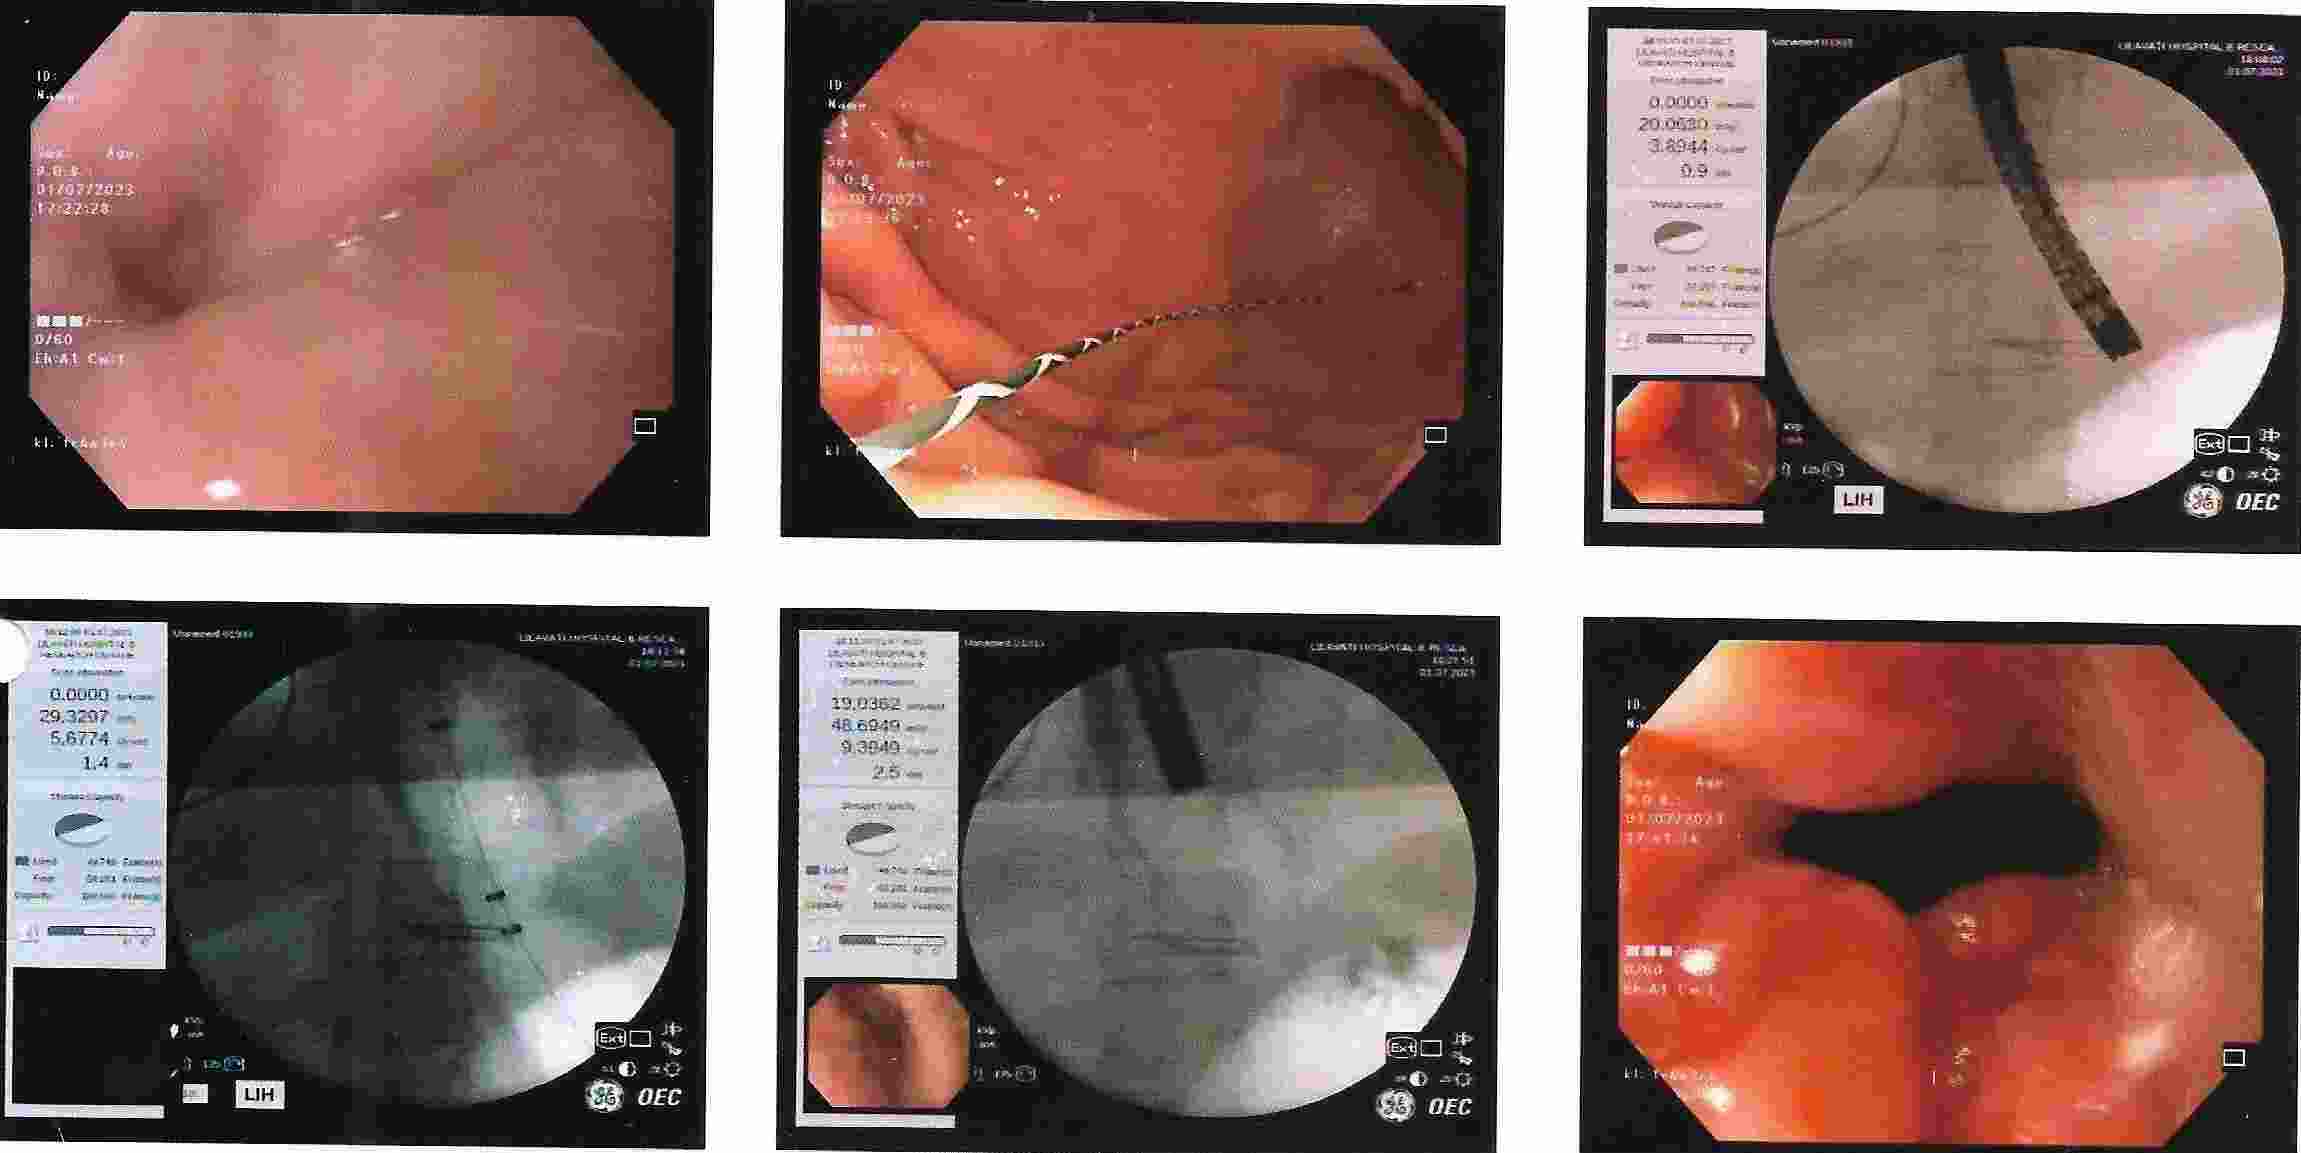

Strong contractions of the food pipe is known as dysmotility of esophagus and an unusual condition known

as Achalasia Cardia due to powerful contraction of the valve of the esophagus at its lower end which

can cause difficulty in swallowing.

Achalasia Cardia - Balloon Dilatation

Achalasia Cardia - Balloon Dilatation

Achalasia Cardia - Balloon Dilatation

Achalasia Cardia - Balloon Dilatation